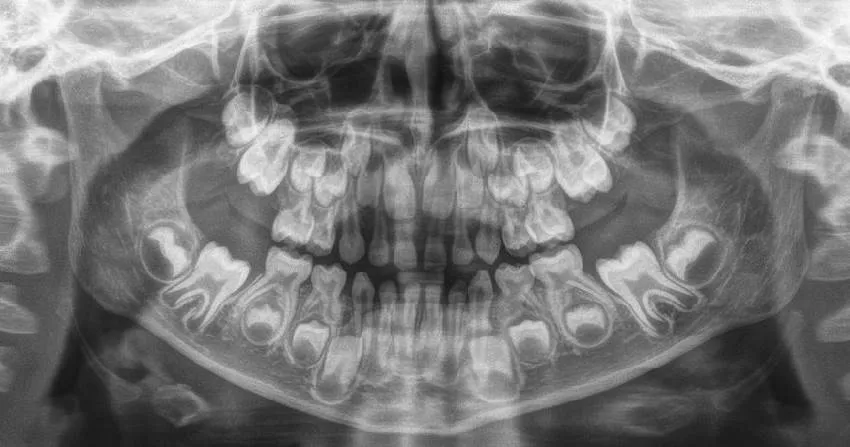

Перед началом ортодонтического лечения или во время активного прорезывания постоянных зубов выполняется панорамная ортопантомограмма. Этот вид визуализации позволяет взглянуть на все зачатки зубов на снимке, а также на молочные зубы, представляя полную картину зубного ряда и челюсти.

Для точного выявления клинической ситуации важно провести компьютерную томографию или сделать прицельный снимок, так как может оказаться, что за молочным зубом находится несколько зачатков постоянного зуба, что можно увидеть только на рентгенограмме.

У человека в жизни присутствует два набора зубов: первые — временные, необходимые для роста, и вторые — неподвижные, которые остаются с ним на всю жизнь. В процессе развития и формирования черепа наш организм использует молочные зубы, которые затем сменяются постоянными.